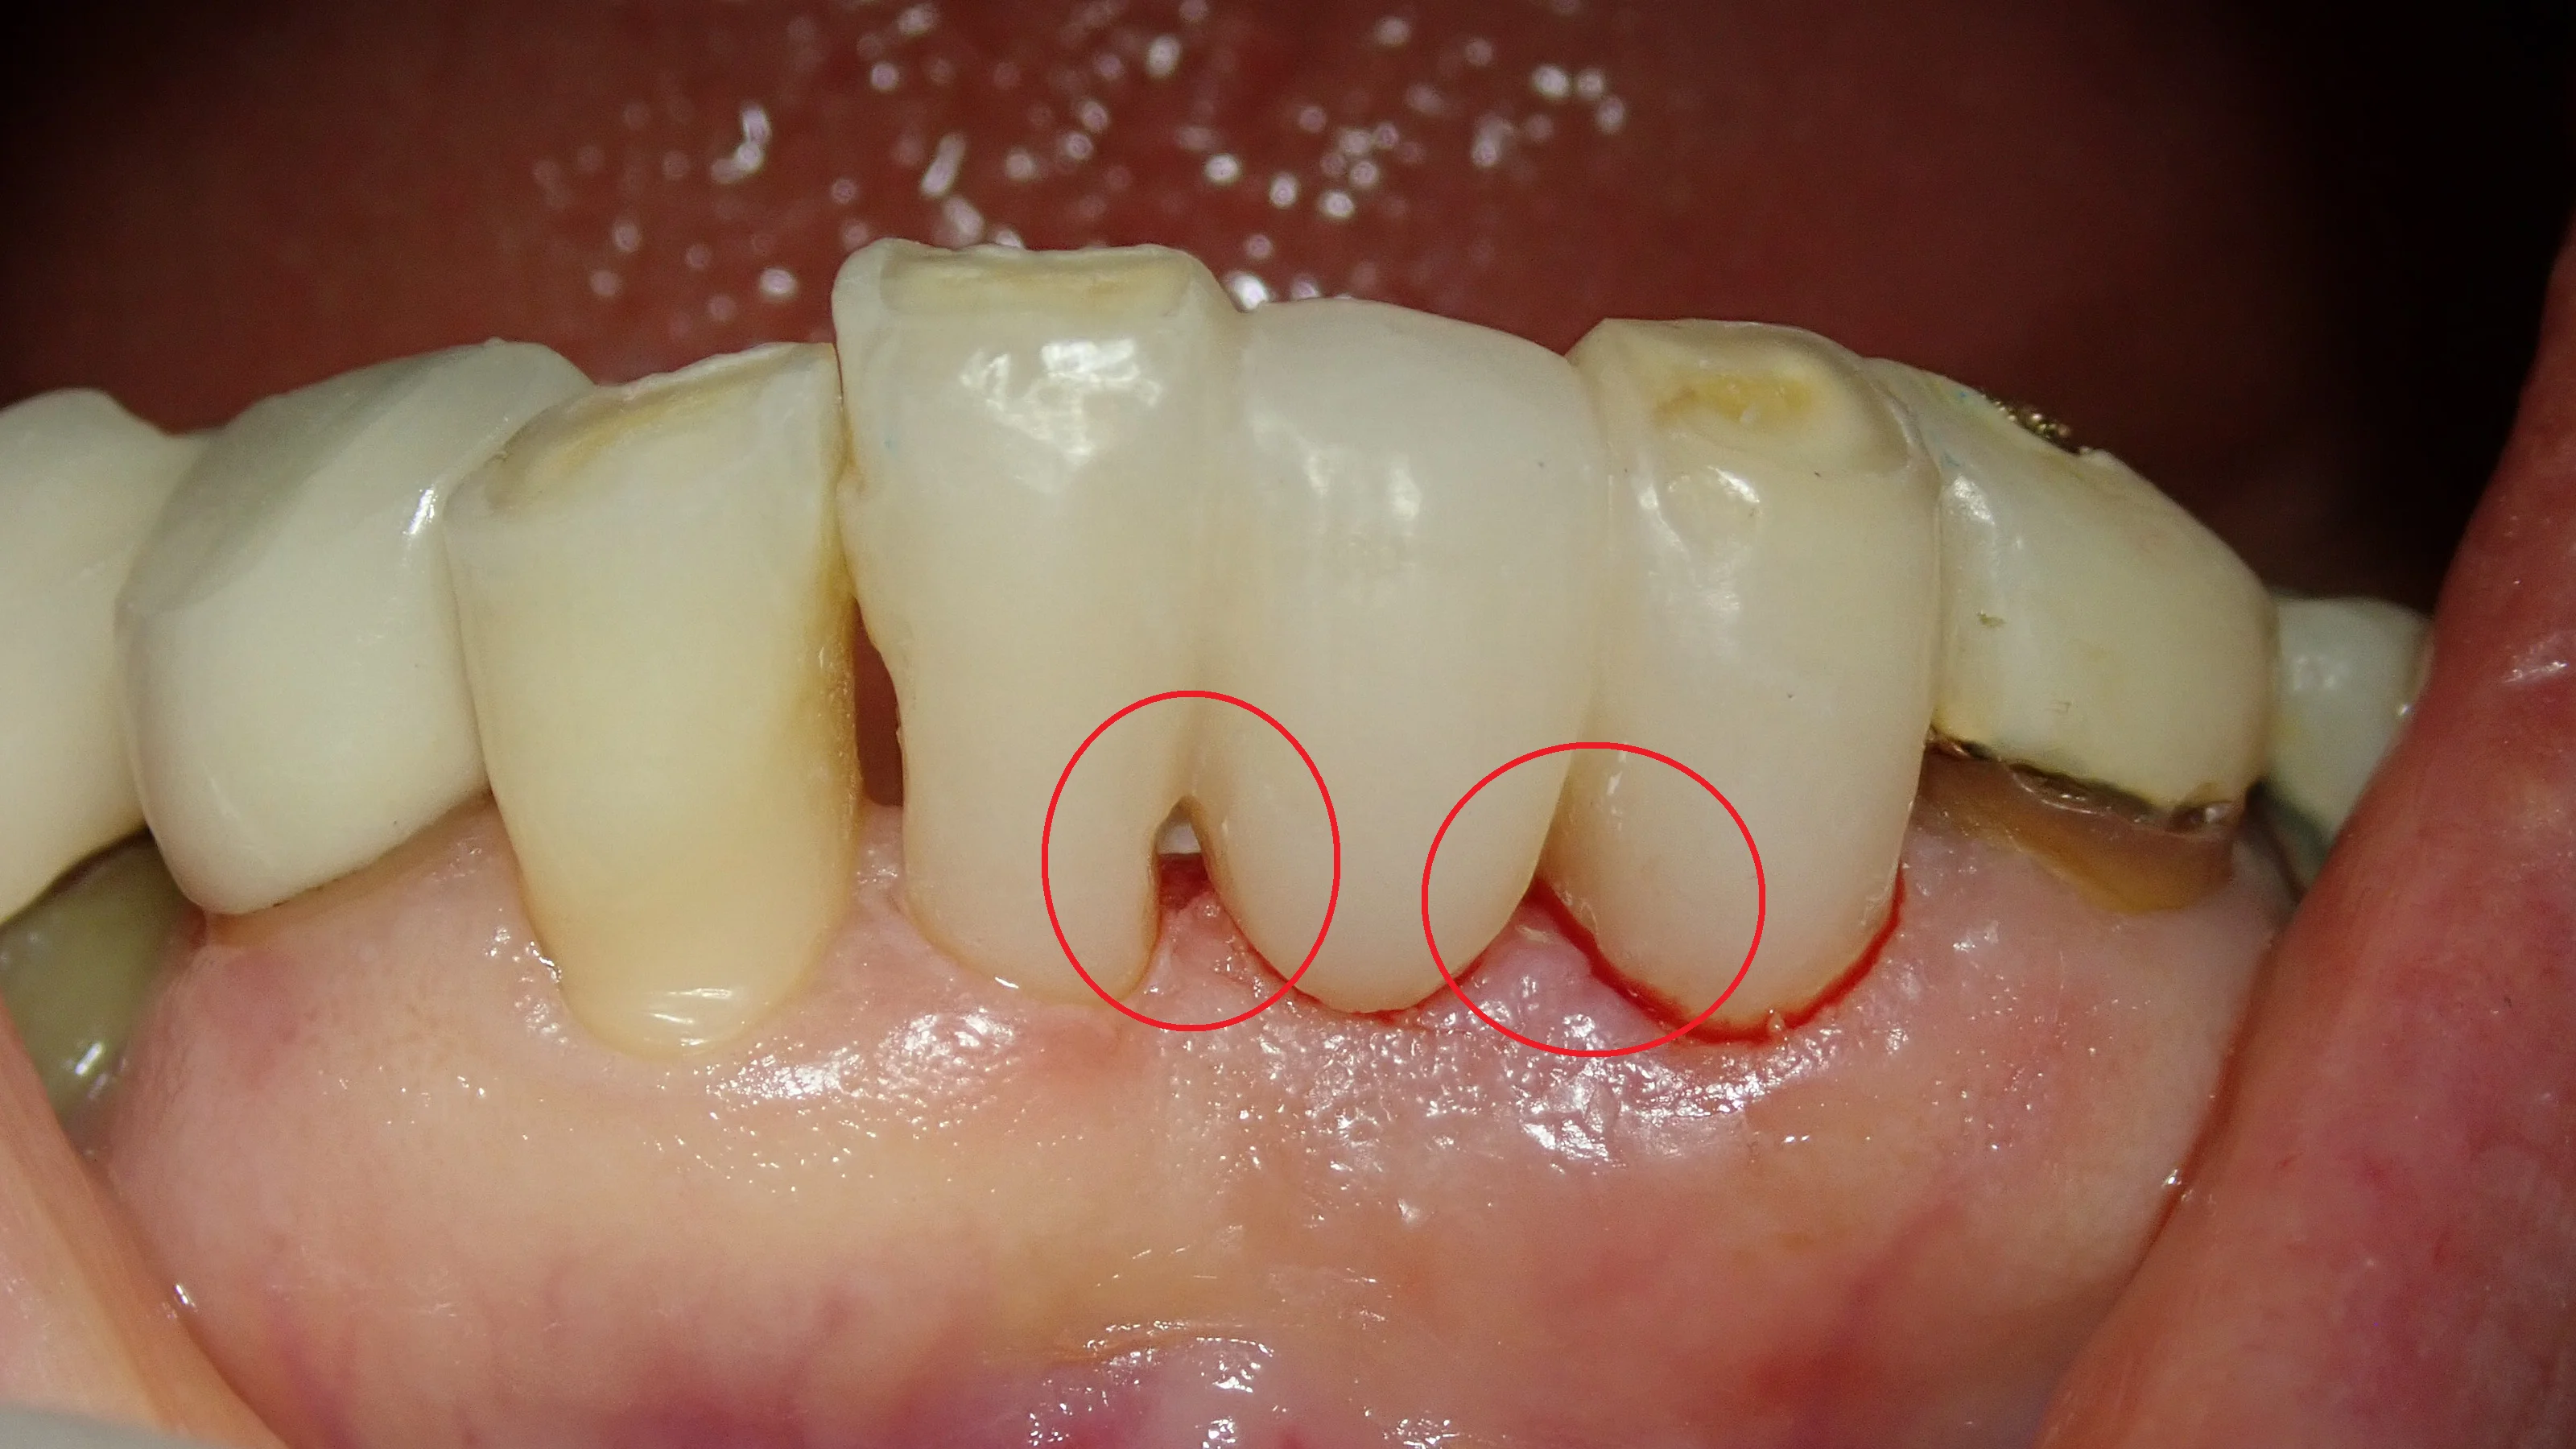

スーパーボンドを外した状態の歯がこちら。

非常に綺麗にブラッシングされているので、除去した時点での出血などはほとんどなし。 歯石が付いていたのでそれを取ったため、若干出血していますが、触らなければ出血は全くしない状況でした。